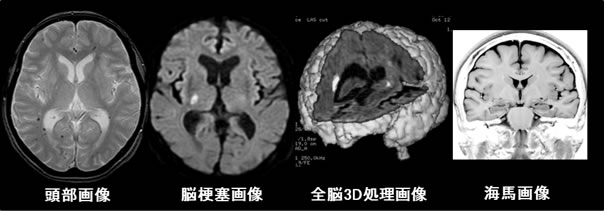

頭部画像では、初期の梗塞(過去に起こした梗塞も)や微細な出血、腫瘍などの診断に有用です。

また、脳全体の委縮を観察することで認知症の初期判断にもつながります。さらに全脳を3Dにて画像化したり、海馬、内耳(耳鳴り)などの脳の中枢を観察することができます。